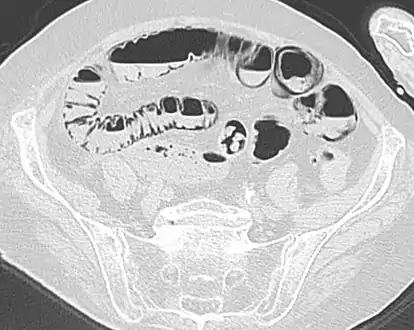

Pneumatosis intestinalis in computed tomography with intestinal ischemia. Lung window for better representation of the gas deposits in the intestinal walls.